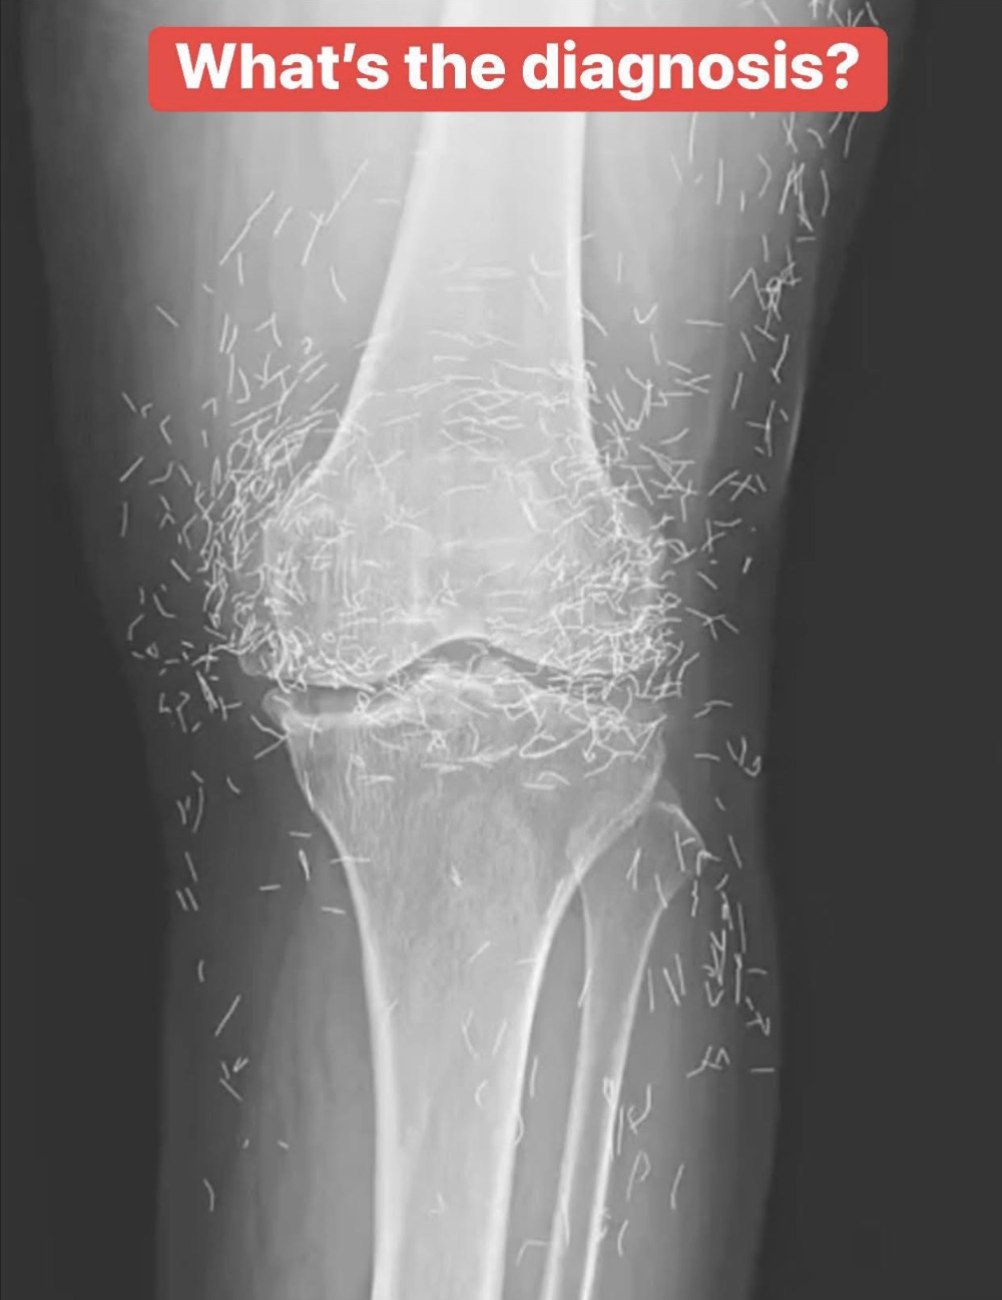

Doctors find “gold mine” in woman’s knees

Doctors Find “Gold Mine” in Woman’s Knees — and the Discovery Left Them Stunned What started as a routine medical examination turned into a remarkable discovery when doctors examining a woman’s knees found an unusual substance that appeared gold-like in color and consistency. While headlines quickly dubbed it a “gold mine,” the real story … Read more